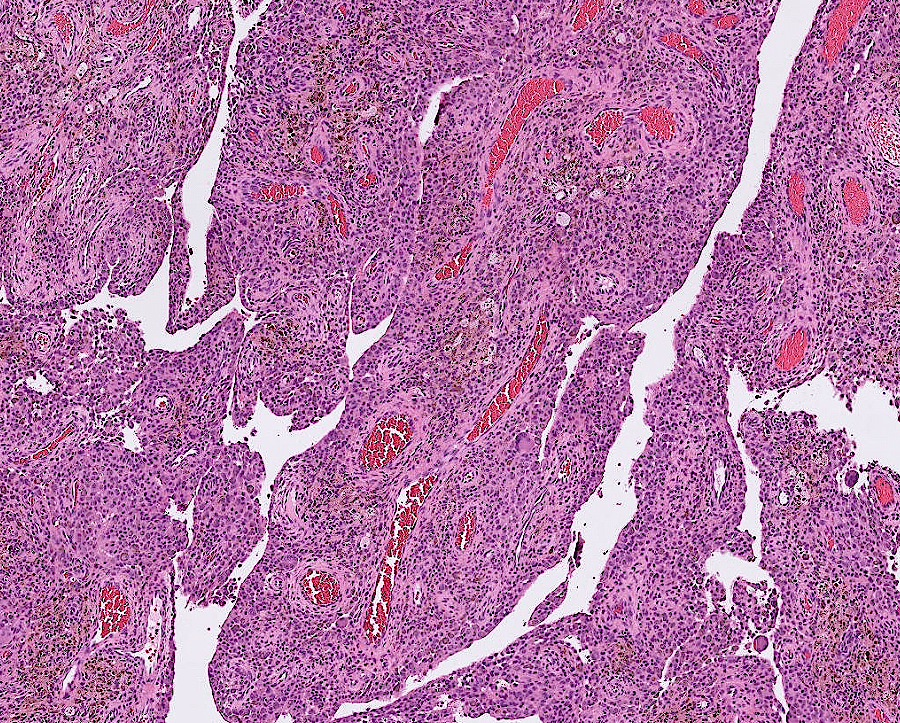

lung adenocarcinoma

colon cancer

endometrial cancer